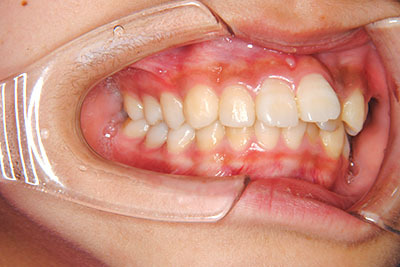

小学生高学年や中高生で矯正治療を考えている方へ

歯が乳歯から永久歯に生え変わった小学生高学年や、中高生でも矯正治療に手遅れということは全くありません。

成長中の顎の骨を矯正できたり、この時期の矯正はおとなになってから矯正治療を始めるよりも短期間で済むことがほとんどです。当院だとおおよそ1年で動的治療(マルチブラケット装置をつける期間)が終わることが多いです。